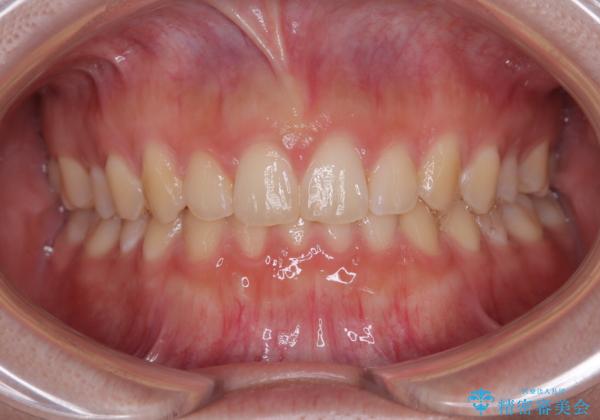

最終的には隙間は全て閉じ、綺麗な仕上がりとなりました。